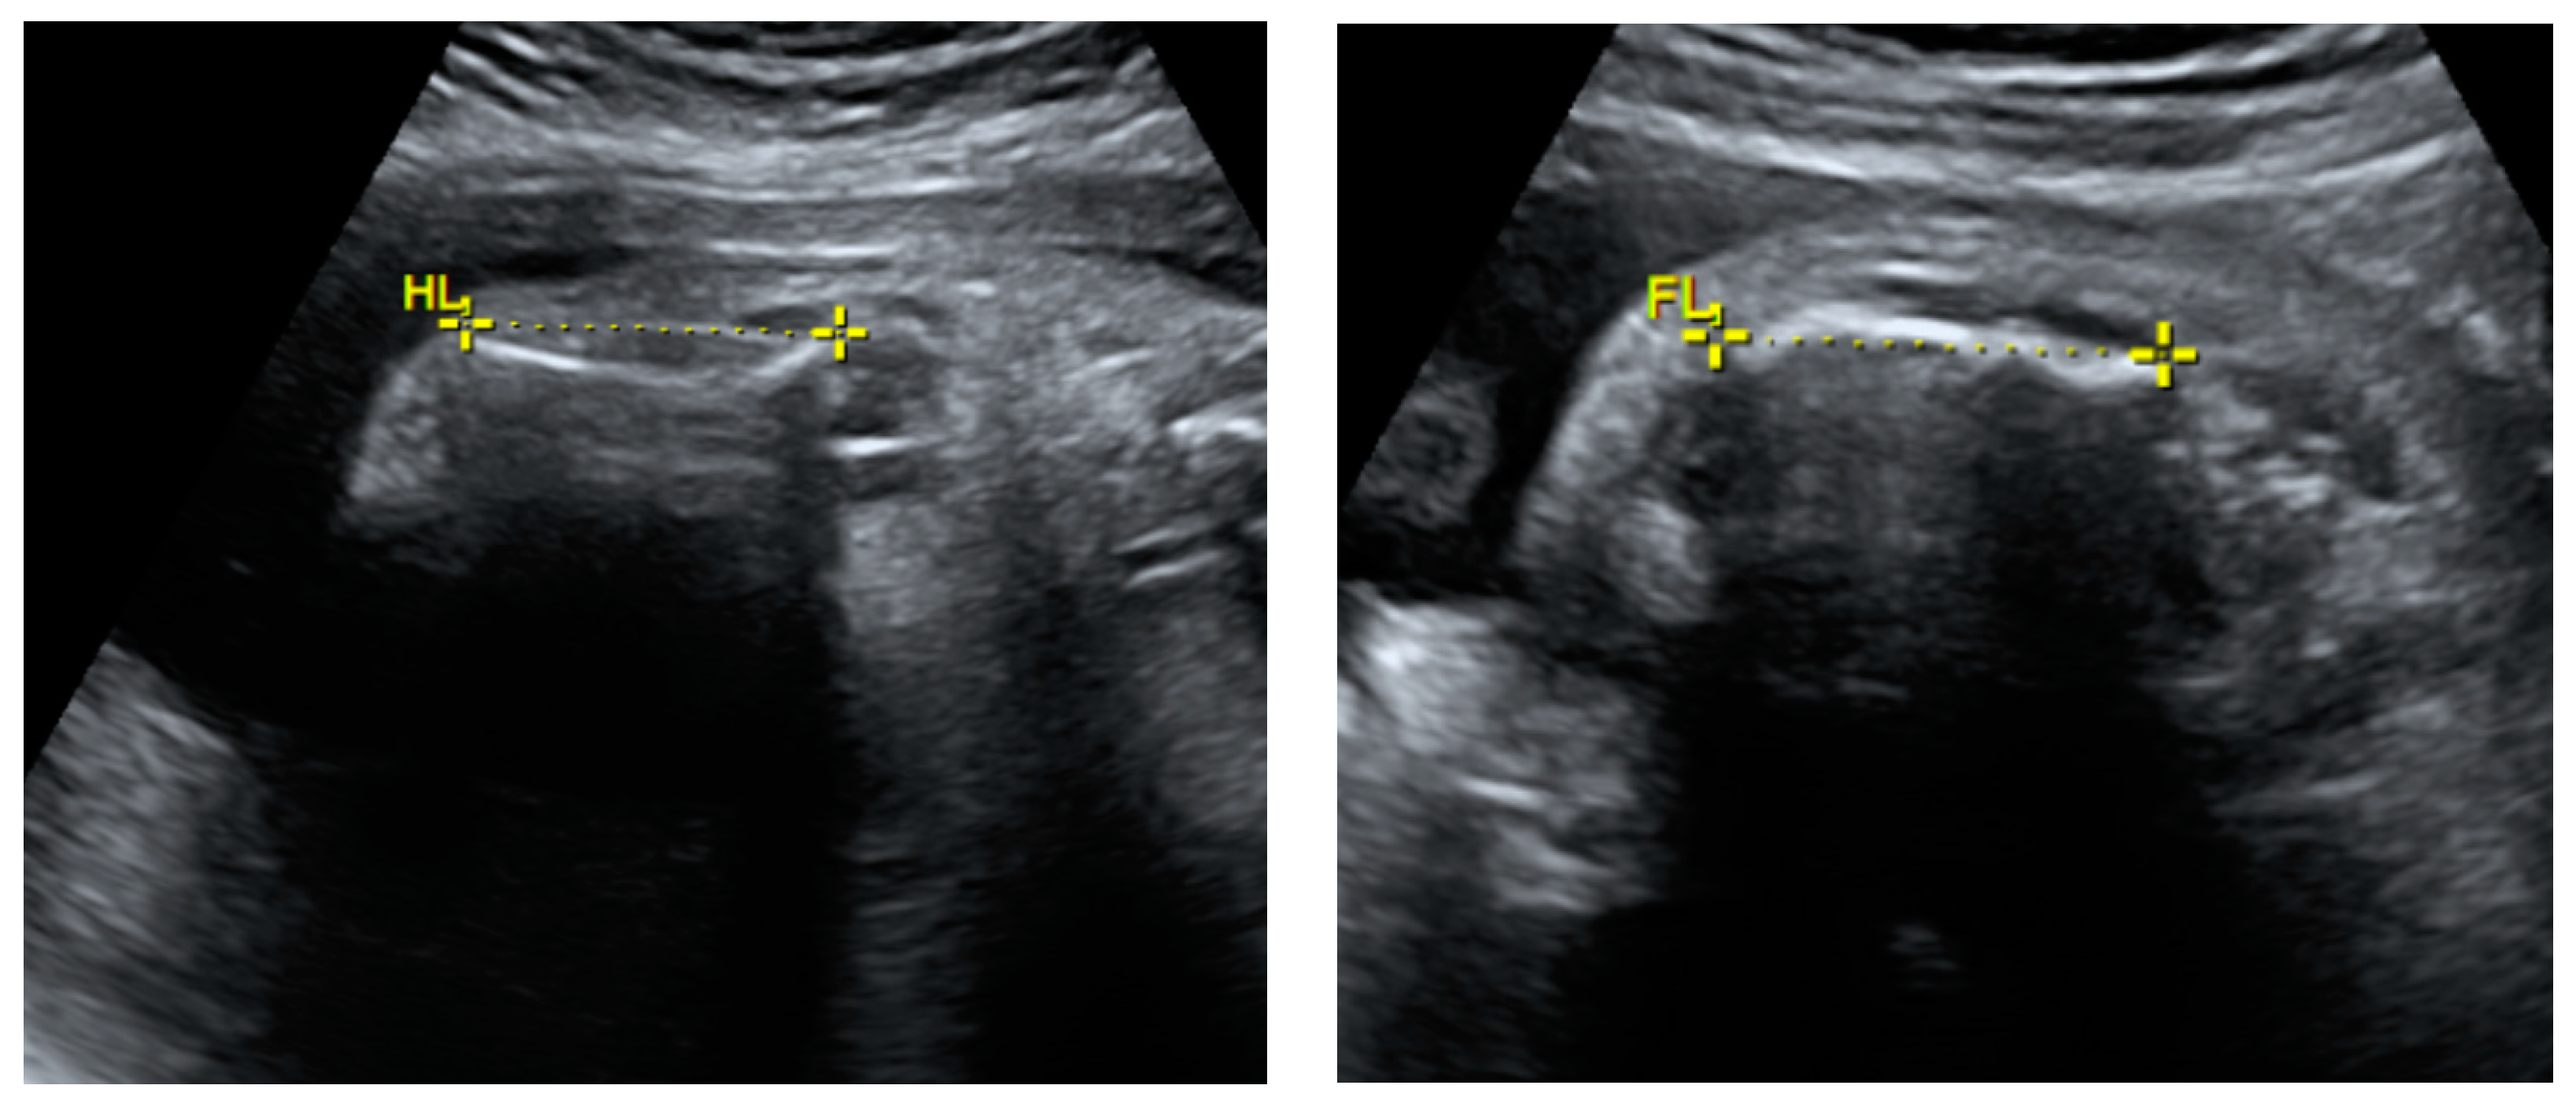

2.1. Prenatal Findings and Further Pregnancy Care